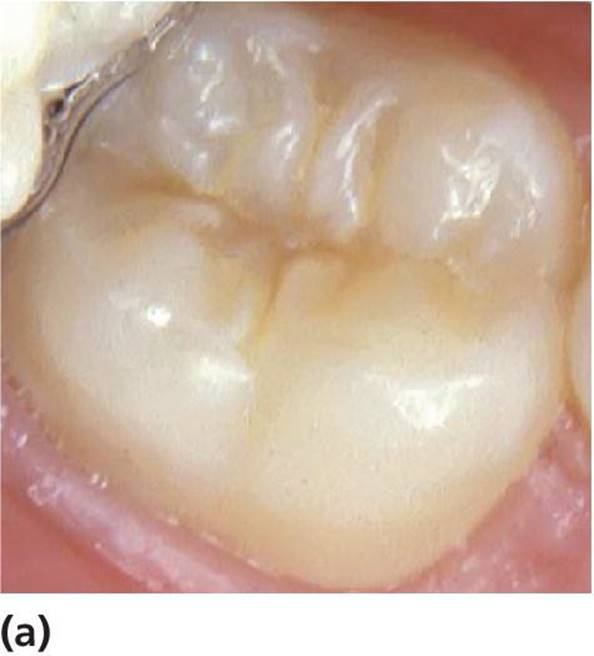

It is likely that the extensive use of fluorides has led to a change in the clinical appearance of pit and fissure caries as well as of approximal caries. The finding of a relatively intact enamel surface hiding a dentin lesion is not uncommon (Figure 12.8). Continuous fluoride supply seems to delay the progression of the caries process in enamel as well as the breakdown of the enamel surface over the dentinal lesion. This phenomenon is sometimes called occult caries [21].

Figure 12.8 Hidden caries under a seemingly sound occlusal surface of a permanent lower second molar in a 14‐year‐old. (a) Visual–tactile examination of the surface did not reveal any clear signs of caries. (b) The bitewing radiograph shows, however, an obvious radiolucency in the dentin. The presence of soft carious dentin was confirmed at drilling.